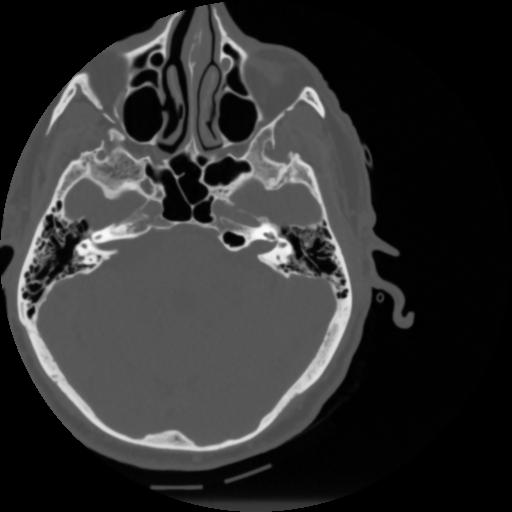

4 CEREBRO,,Vol,0.5,CEREBRO,,